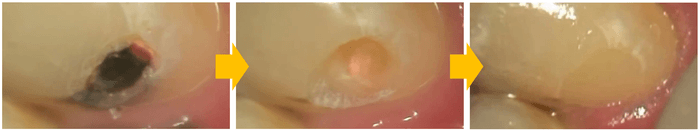

どんなに技術に優れた名医が、虫歯をドリルで取り除く治療を施しても、ドリルの鋭い刃により、虫歯になっていない正常な歯質、言わば取り除かなくても良い健全な歯を虫歯と一緒に削り取ってしまいますが、レーザーは正常な歯質に水分を含んだ虫歯の部分だけを取捨選択して取り除く事が出来る究極の低侵襲治療です。しかもレーザーの熱により残った歯質が強化され虫歯になりにくく成るのです。

マイクロスコープで視野を数十倍に拡大することで、肉眼では見えない微細な虫歯や感染部位を特定できます。「悪い部分だけを確実に取り除き、健康な歯を極限まで残す」という低侵襲な治療が実現します。

ドリルなどの回転切削器具は、どうしても特有の不快な振動や機械音は発生してしまします。また、振動や勢いで健康な歯質まで削ってしまうリスクがあります。レーザーを使用すれば、ターゲットとなる組織だけを蒸散させることができるため、隣接する健康な歯や歯肉を傷つけるリスクを最小限に抑えられます。

マイクロスコープで見つけたばかりの微細な異変(初期虫歯や小さな亀裂など)に対し、早期発見・早期治療の精度が飛躍的に高まります。その場でレーザーによる処置(殺菌や再石灰化の促進)を行うことができます。